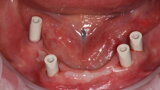

Fig. 10: Scanbodies in situ.